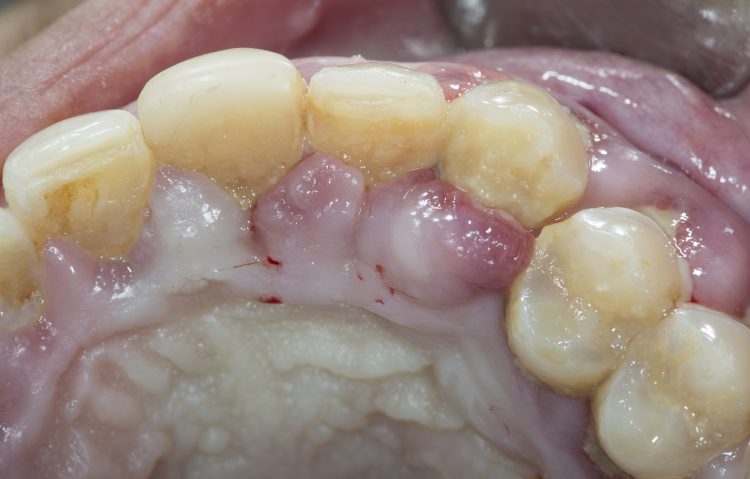

- Gum redness and swelling: The gum color turns bright red, the texture becomes soft, and there is pain when touched.

- Gingival recession: The gums gradually recession towards the root of the tooth, exposing the root of the tooth and making it appear longer.